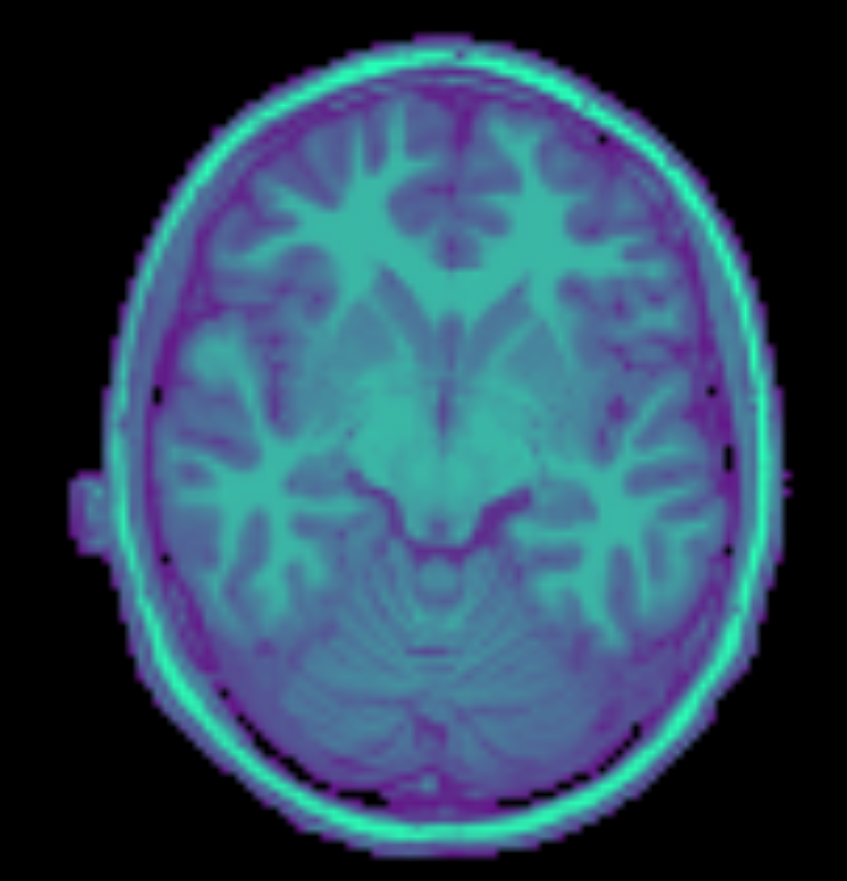

Brain Camera

MRI Scanner

Fetal MRI

Image Volumes

2D

3D